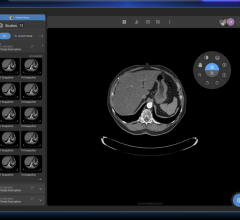

The conferencing system used in Hammersmith combined MultiSense's telemedicine infrastructure with Barco's surgical display technology. The system provided viewers with a real-time, two-way communication link between the operating theater and the conference room, thereby enabling detailed discussions while the procedure was being performed. Thanks to the surgical display's intelligent picture-in-picture functionality, the audience had a high-definition view of the operation on screen, including local and remote camera images, the patient's vital signs, and the endoscopic video of the operation.

“The MultiSense medical cart provides a very efficient and comfortable way of visualizing and sharing images and data, both inside and outside of the surgery suite,” said Dr. Punjabi. “The most important aspect of the solution, however, is the excellent quality of the patient images. The Barco MDSC-2124 surgical display guarantees excellent performance under high ambient light conditions, and allows for detailed discussion during the procedure. Moreover, at 1,920 x 1,200, its high-definition resolution improves depth perception, enhances hand-view coordination and allows for better patient care overall.”